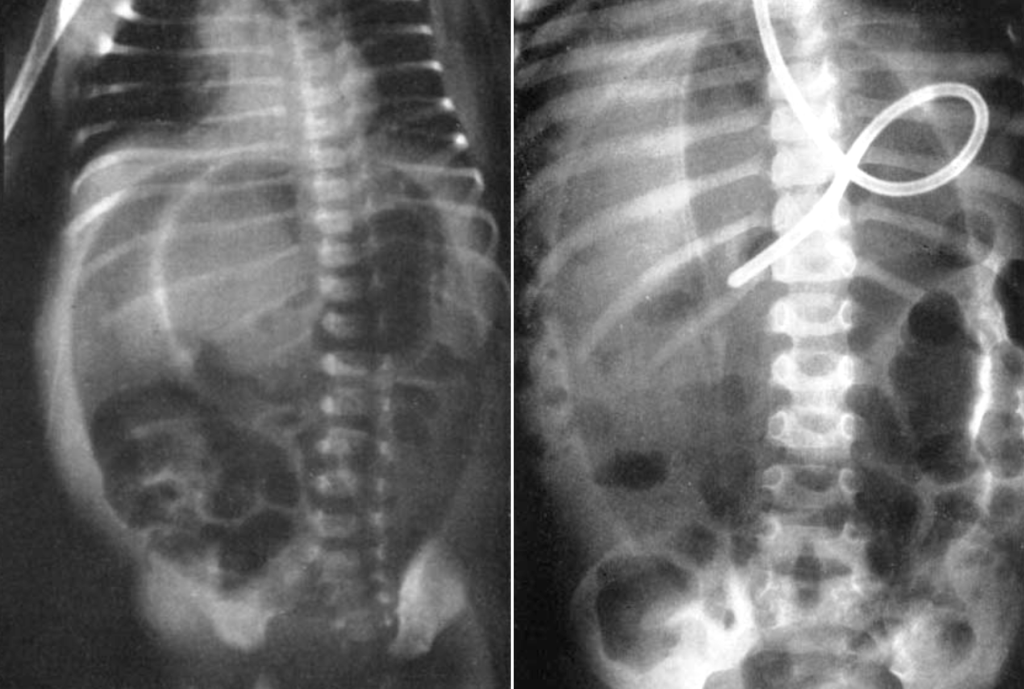

1960 – Roscoe E. Miller (1918-1984) of the Indiana University School of Medicine described the “air dome” sign in a series of infants with gastric, duodenal, or colonic perforation. This was based on a large review of supine radiographs from patients too ill for erect imaging.

Figure 2: Supine radiograph in a 4-year-old showing similar air dome, with confirmed duodenal perforation at autopsy. Miller 1960

Miller’s sign emphasised the early and specific recognition of free air in neonates using only supine films, significantly aiding diagnosis when other signs were absent or patients were non-ambulatory.

Confirmatory upright films may be taken, but it is unnecessary if the “air dome” sign is seen on the supine view. The “football” or “air dome” sign is pathognomonic and leads to early diagnosis and surgical intervention…The characteristic oval line of the “air dome” divided by the streak of the falciform ligament is pathognomonic.

Miller, 1960